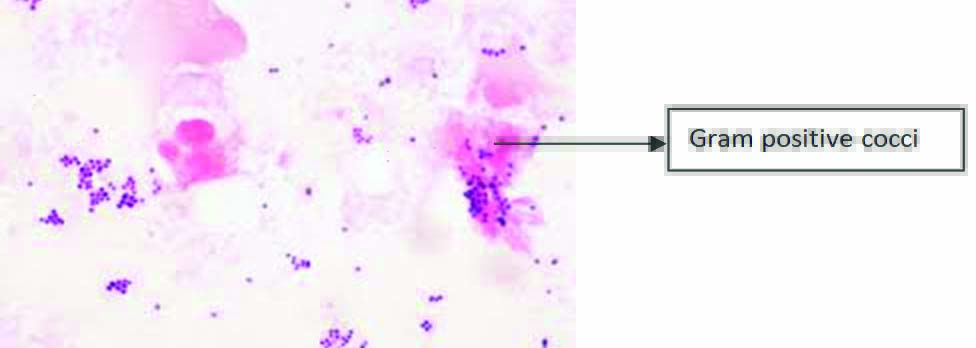

The samples were labeled with date, time, patient’s name, age and sex. Two pus samples were collected; the first swab was used for direct smear stain examination [Table/Fig-1] and the second swab for culture on 5% Sheep Blood Agar (SBA), Mac-conkey Agar (MA) and Chocolate Agar (CA). Different types of colonies in Nutrient Agar (NA) and MA is shown in [Table/Fig-2]. The SBA, MA were incubated at 37°C for 24 hours, whereas CA was incubated in candle jar generating 5% Carbon Dioxide (CO2) at 37°C for 48 hours [10]. The isolates identification was done on the basis of standard microbiological techniques like microscopic stain examination, colony morphology and biochemical testing [10]. The antibiotic susceptibility testing was done in-vitro on Muller Hinton agar using Kirby Bauer disc diffusion method using 0.5 McFarland culture suspension of isolate as per Clinical and Laboratory standard Institute (CLSI) recommendation [11]. The antibiotics used for testing were ampicillin (10 mcg), amikacin (30 mcg), amoxycillin/clavulanic acid (20/10 mcg), ceftriaxone (30 mcg), gentamicin (10 mcg), levofloxacin (5 mcg), meropenem (10 mcg) and vancomycin (30 mcg).

Direct gram stain of ear swabs of patients with CSOM showing gram positive cocci (X1000).